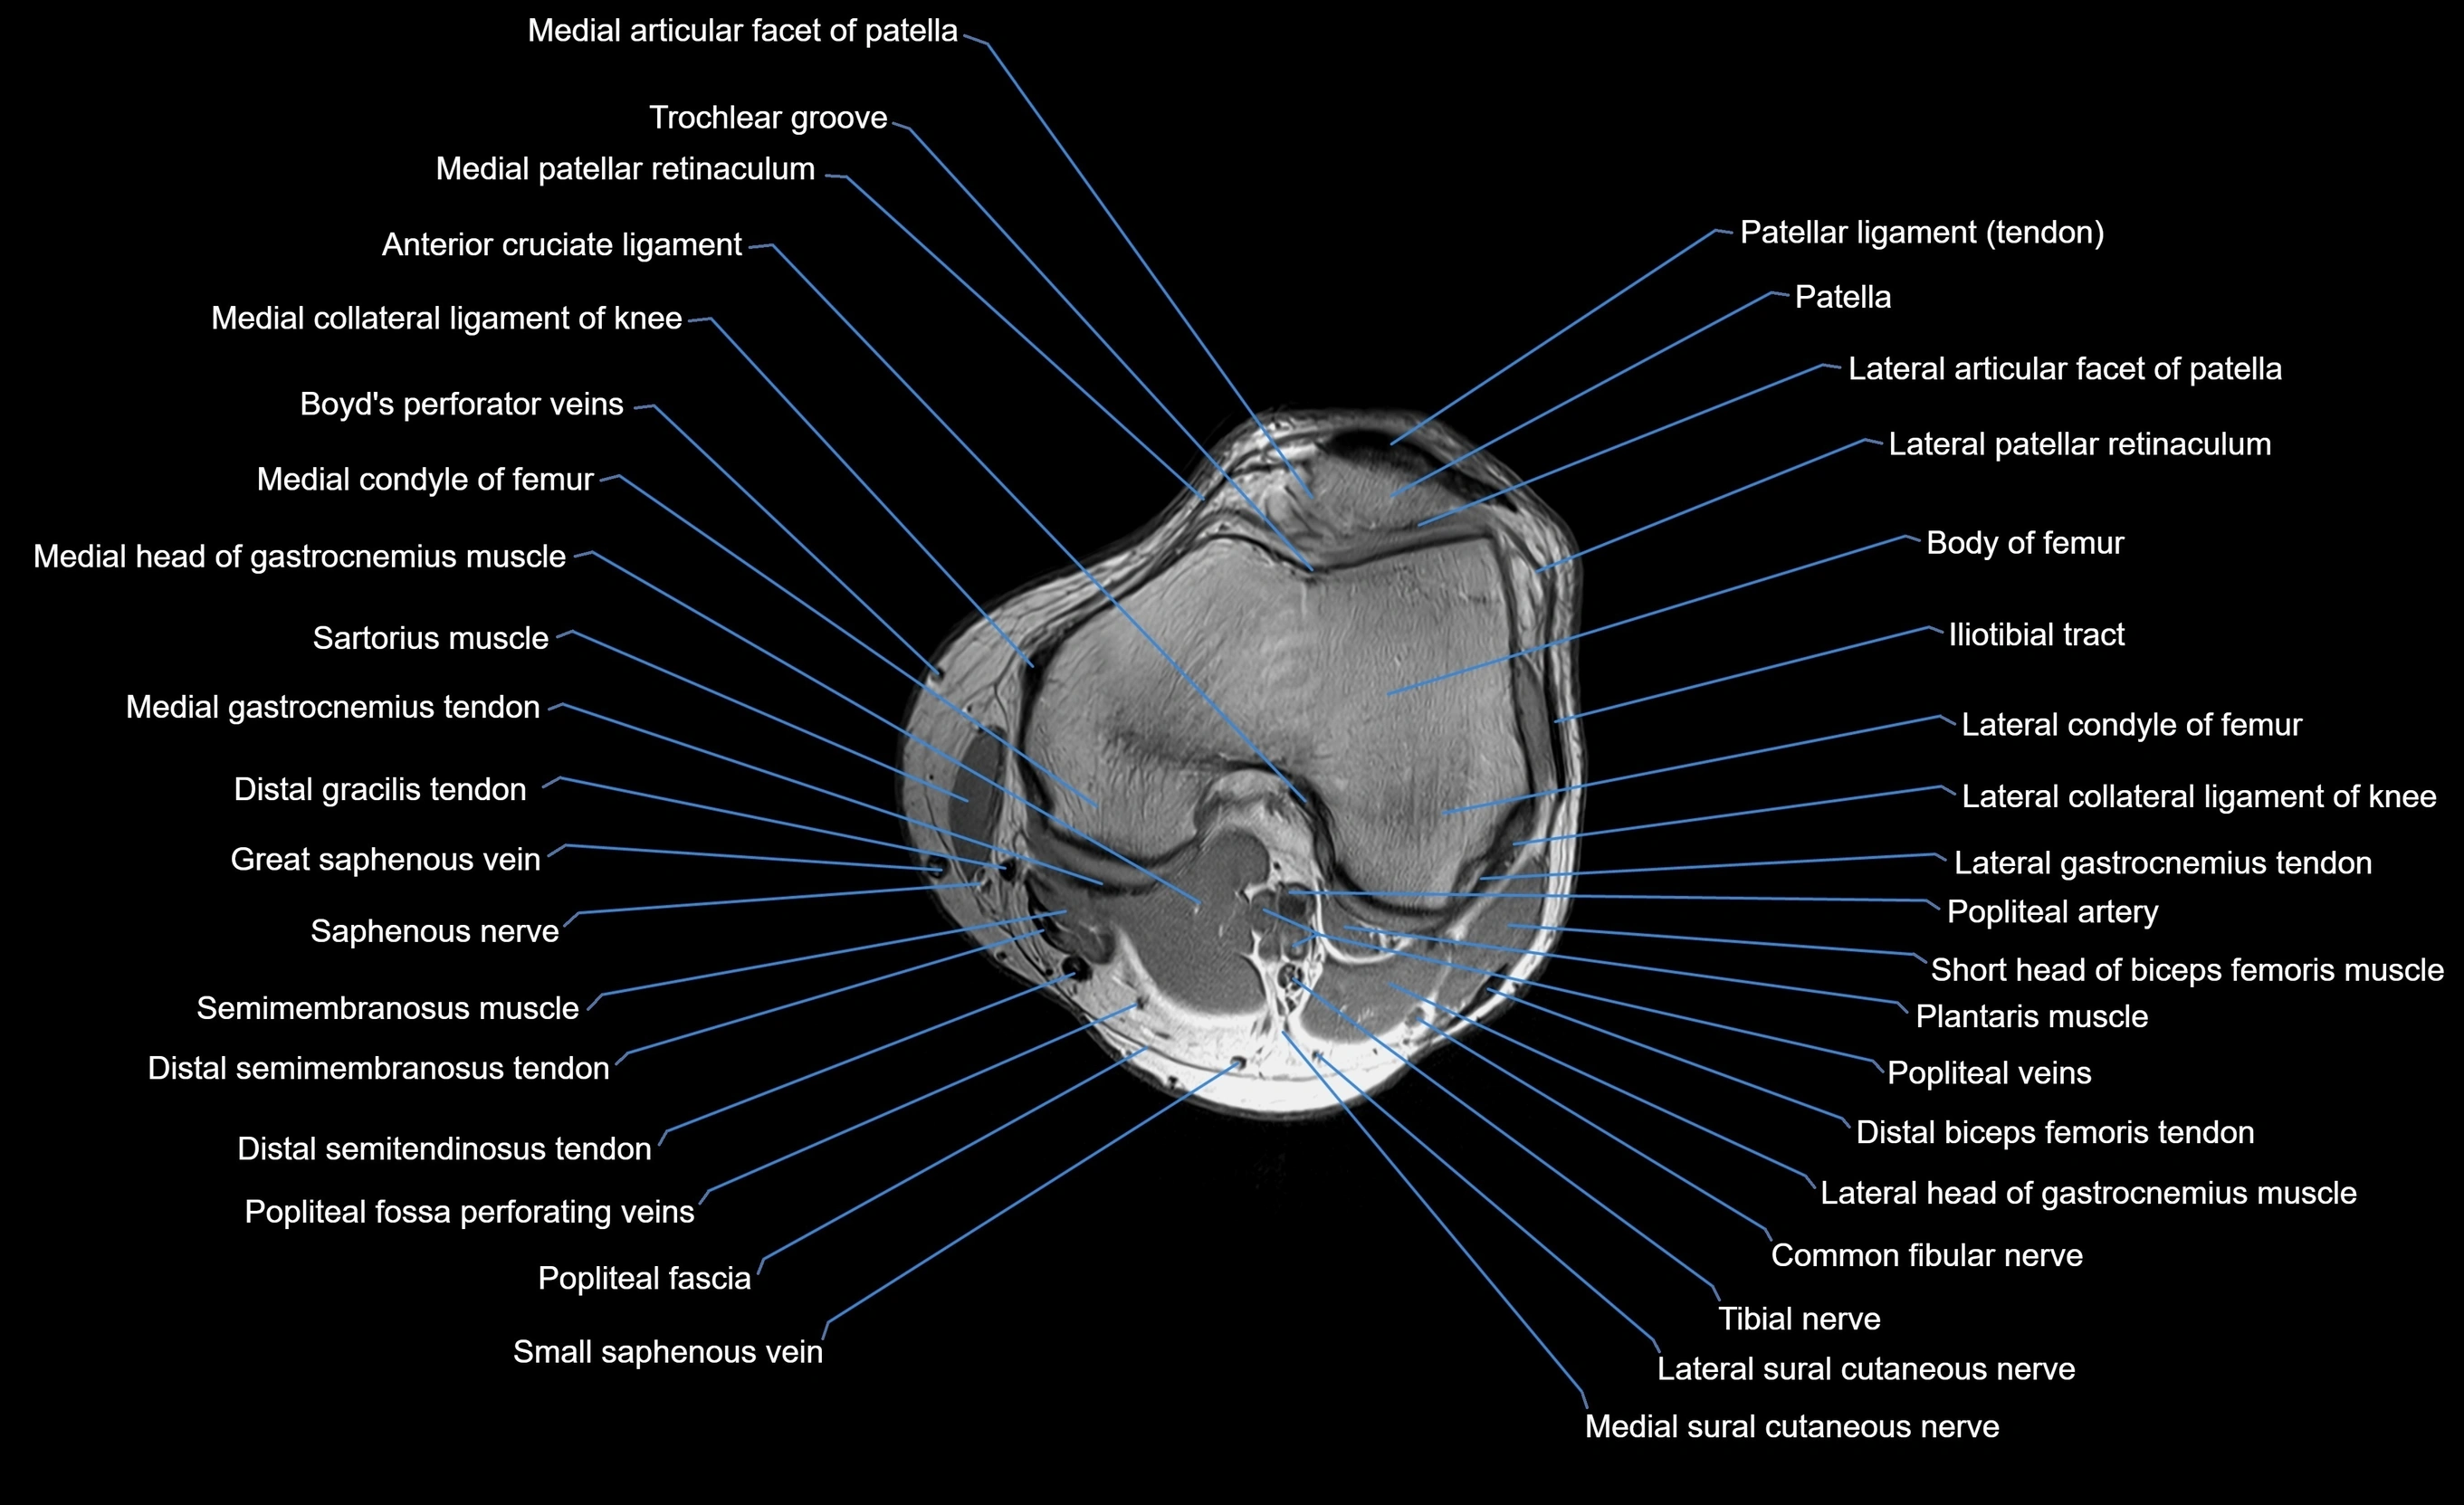

MRI image